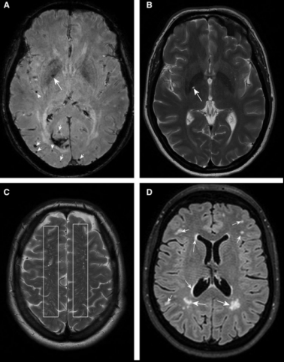

实例二:磁共振成像能够清晰呈现大脑内部结构,适用于观察和分析微出血、腔隙梗死等脑部病变的特征及分布情况(如图6所示),为脑卒中疾病的诊断提供影像依据。

图6:微出血和腔隙梗死等常见小血管疾病的磁共振成像[6]